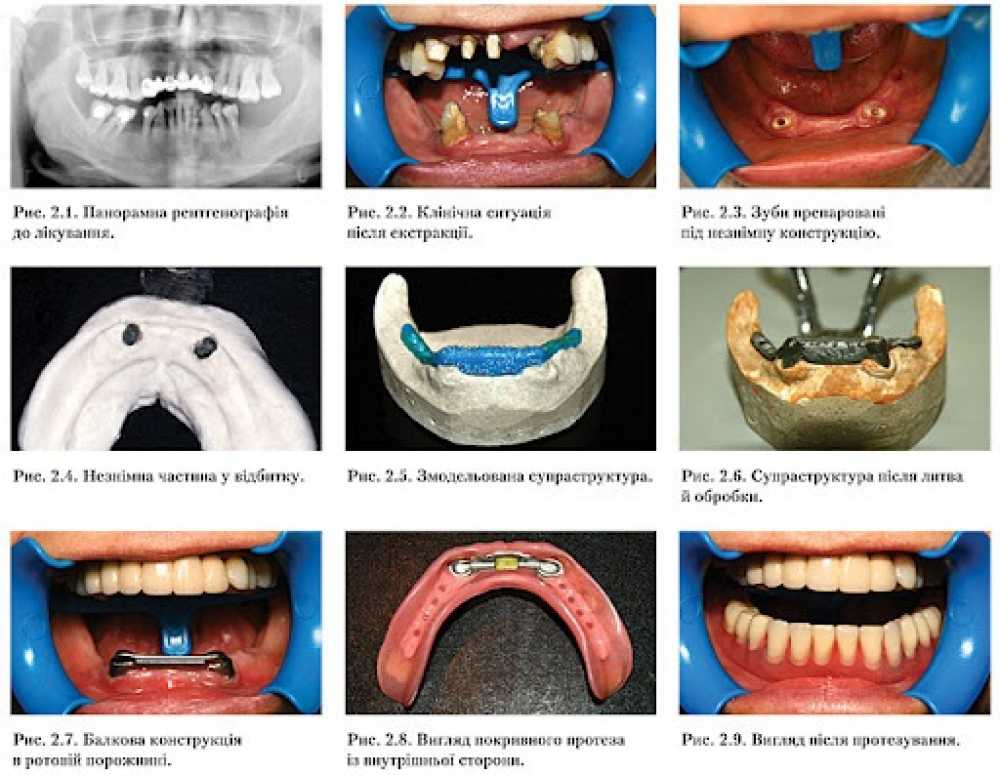

Балкові конструкції у протезуванні: теорія та цифрові рішення

Модуль 1.

База. Підготовчі етапи

Модуль 2.

Все про дизайн балок в Exocad

Модуль 3.

Все про дизайн балок в Blender

Модуль 4.

Вторинна структура на балках

Модуль 5.

Бонус. Пресс на балці